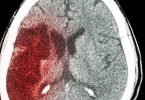

外伤脑出血一般需要住院14-30天,具体时间与出血量、损伤部位、并发症及恢复情况有关。外伤脑出血的住院时间主要受临床指标影响。出血量在10-30毫升且位于非功能区时,住院时间通常为14-21天,期间需监测颅内压变化 ...

脑出血引流手术的危险期一般为7-14天,具体时间与出血量、手术时机、患者基础健康状况等因素相关。术后1-3天是急性危险期,此时可能发生再出血、脑水肿加重或颅内压急剧升高。此阶段需密切监测生命体征,通过影像学 ...

脑出血后左侧肢体不能动通常由出血部位压迫运动神经传导通路或脑组织损伤导致。主要原因包括内囊出血、脑干出血、大脑半球运动区损伤、脑水肿压迫神经以及继发性脑缺血等。1、内囊出血内囊是大脑皮层与脊髓之间神经 ...

外伤颅内出血的症状主要有头痛、呕吐、意识障碍、肢体无力、瞳孔异常等。外伤颅内出血通常由头部受到外力撞击、脑血管畸形、高血压等因素引起,可能伴随颅内压增高、脑组织损伤等症状。1、头痛头痛是外伤颅内出血的 ...